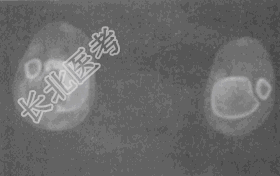

- 单项选择题女性,22岁, 小腿疼痛2个月。X线片和CT片如图。应首先考虑的诊断是